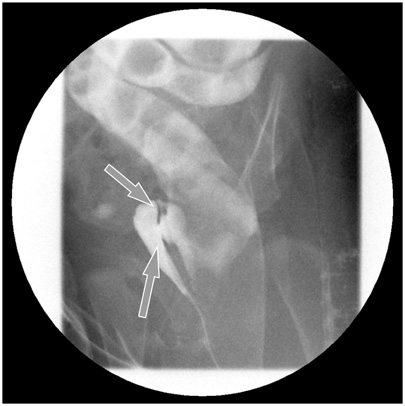

Fig. 2). A catheter was inserted through the ectopic anus, and an intraoperative contrast study and sigmoidoscopy were performed. A parallel tubular duplication with a common wall was found. The common wall extended 5 cm from the anal verge to the sigmoid colon and then 20 cm to the level of the proximal sigmoid colon. Proximally, the anterior duplication and normal colon merged and formed a normal colon. Because most of the stool moved through the anterior duplication and because the diameter of the anterior duplication was larger than that of the normally located colon (

Fig. 3), complete resection of both the anterior duplicated bowel and posterior native bowel up to the merging point with colo-anal anastomosis was performed (

Fig. 3Intraoperative findings. (A) The intraoperative contrast study revealed that the contrast injected via the anterior anorectal duplication filled the normal colon and rectum and that there was a connection between the duplication and the normal colon at the level of the proximal sigmoid colon. (B) Intraoperative sigmoidoscopy at the merging point revealed that a catheter inserted via the anterior anorectal duplication could be observed by a scope inserted via the normal anus.